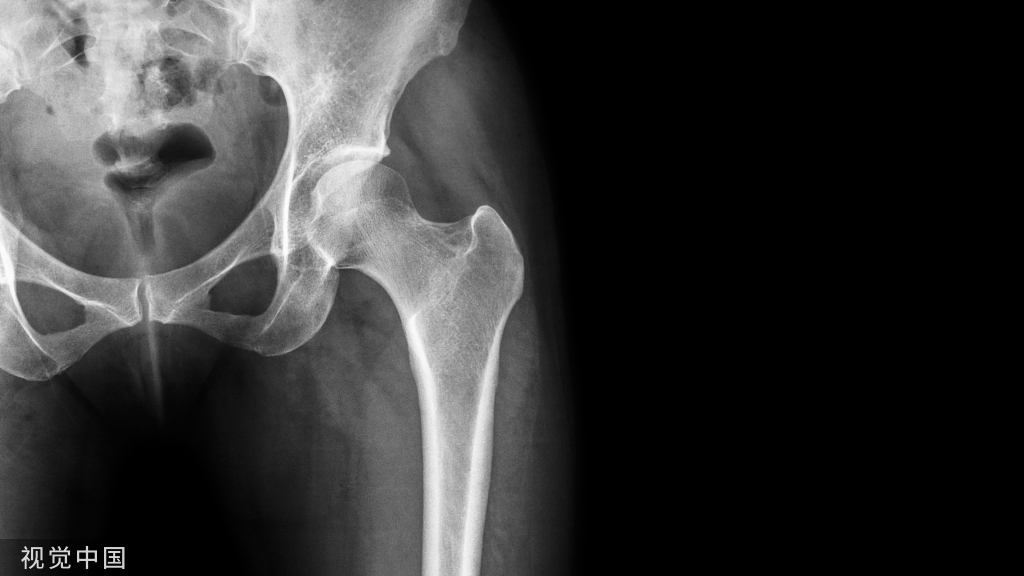

28H 型椎体

H 型椎体(H-shaped vertebrae),也称为林肯原木椎体(Lincoln log vertebrae)

H 型椎体是指椎体终板中央边界锐利的凹陷,使得椎体呈现字母 H 或者林肯原木样的形状,因而得名。本征象通常用于描述镰状细胞贫血的脊柱改变,偶然也可以见于其他疾病,比如地中海贫血或者戈谢病。这种椎体形态的改变是终板的微血管梗死所致。

典型病例

病例 1,镰状细胞贫血患者,胸椎侧位片示椎体上下终板中部凹陷,使得椎体呈字母 H 样改变。

病例 2,镰状细胞贫血患者,胸椎 CT 矢状位重建骨窗图像示椎体上下终板中部凹陷,呈字母 H 样改变。

引用自:https://radiopaedia.org/articles/ h-shaped-vertebra